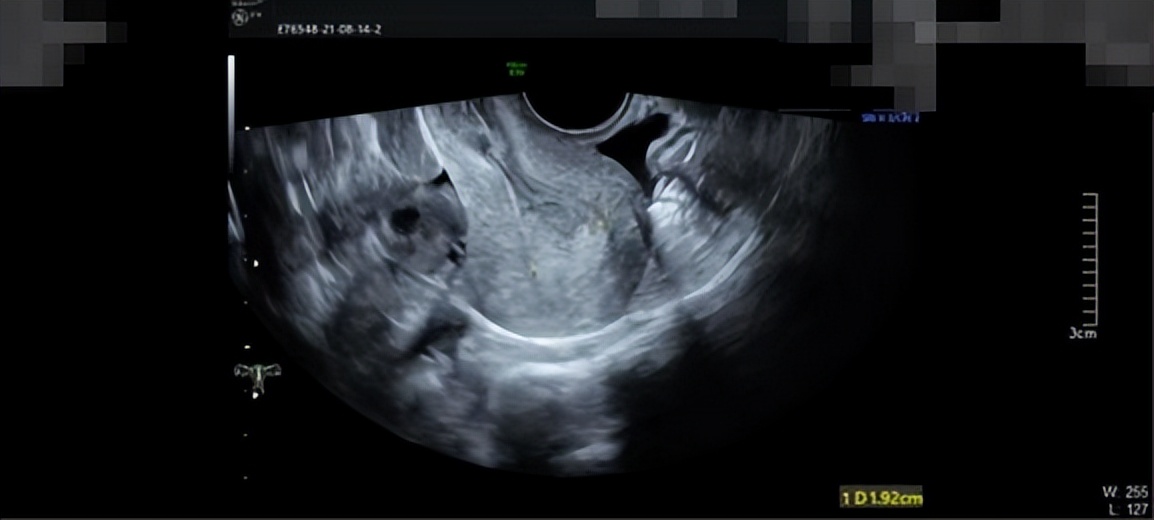

周女士十分焦虑,她问我:“医生,我之前流产过一次,然后现在我又一直出血,我以后不会不能怀孕了吧?我还没有结婚,我还想生个孩子,医生,你一定要帮帮我”我对周女士说:“我们会尽力的”我的内心能够感受到周女士迫切的心情,我想子宫对一个未孕女子的意义重大,我们作为医者,一定要从患者的切身角度去维护好患者最大的意愿。我查阅周女士的病历了解到,周女士在2021年8月初的时候就诊医院B超检查子宫,超声提示内膜厚1.8cm(双层),回声不均,考虑子宫内膜厚,如图1所示,当时给予黄体酮口服12天,情况缓解。在2021年9月,月经第5天时复查,超声提示内膜增厚1.29cm(双层),回声不均,宫腔内见1.1*0.8*0.6cm稍低回声,内见星点状血流,息肉?粘肌?如图2所示。

图2.复查黄体酮治疗后B超结果